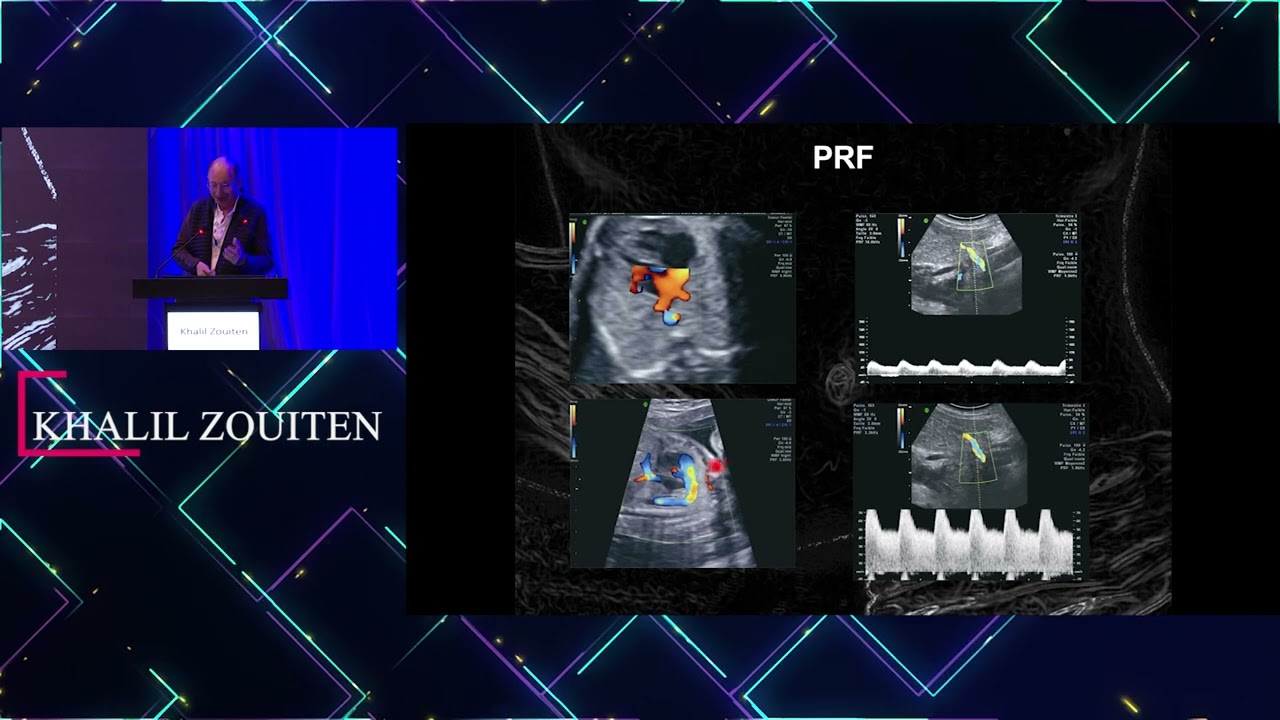

• Les journées d'échographie: Comment réussir son Doppler en obstétrique: Khalil Zouiten

Les journées d'échographie: Comment réussir son Doppler en obstétrique: Khalil Zouiten